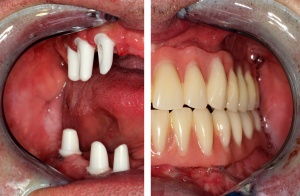

Im August 2012 erfolgten die 3D-gestützte Implantation (6 Implantate, Firma Nobel Biocare, System Active) im Oberkiefer mit Bone Split sowie eine An- und Auflagerungsosteoplastik vom linken Beckenkamm im Unterkiefer nach Entfernung der Miniimplantate (Abb. 3). Nach komplikationsloser Einheilung wurde im Dezember 2012 die Materialentfernung und Implantation im Unterkiefer (6 Implantate, Firma Nobel Biocare, System Active) durchgeführt (Abb. 4). Die Osseointegration verlief ungestört. Aufgrund der ungenügenden Weichgewebssituation im Unterkiefer erfolgte an jedem Implantat bei Freilegung eine Vestibulumplastik mit Einlagerung einer bioresorbierbaren Membran (Firma Botiss, Mucoderm, Abb. 5 und 6). Die endgültige prothetische Versorgung erfolgte durch den truppenzahnärztlichen Kollegen in der Stammeinheit des Patienten (Zahnarztgruppe Nordholz / SanZ Celle) mit einer gaumenfreien implantatgetragenen Teleskopprothese im Ober- und Unterkiefer, die eine festsitzend-herausnehmbare vollständige stomatognathe Rehabilitation des Patienten ermöglichte (Abb. 7 und 8). Er wurde zum halbjährlichen Recall angehalten.

Die endgültige prothetische Versorgung erfolgte im Fachzahnärztlichen Zentrum des Bundeswehrkrankenhauses Hamburg auf Patientenwunsch mit 4 verblendeten Nichtedelmetallkronen (Abb. 14). Einer erneuten Weichgewebsplastik zur Konturverbesserung steht der Patient ablehnend gegenüber.